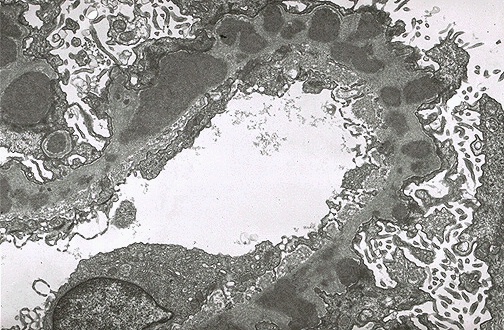

| By electron microscopy in membranous glomerulonephritis, the darker electron dense immune deposits are seen scattered within the thickened basement membrane. The "spikes" seen with the silver stain represent the intervening matrix of basement membrane between the deposits. |